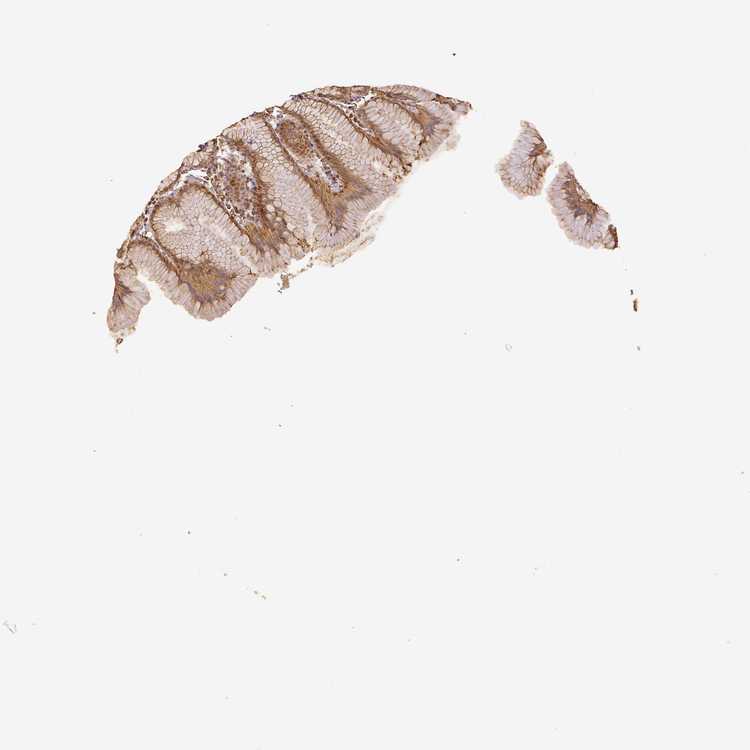

TISSUE PRIMARY DATA STOMACH Show tissue menu

STOMACH 1 - Antibody stainingi

Antibody staining in the annotated cell types in the current human tissue is reported as not detected, low, medium, or high, based on conventional immunohistochemistry profiling in selected tissues. This score is based on the combination of the staining intensity and fraction of stained cells.

Each image is clickable and will lead to virtual microscopy that enables deeper exploration of all samples and also displays staining intensity scores, fraction scores and subcellular localization as well as patient and tissue information for each sample.

Antibody HPA002868Antibody CAB009822Antibody CAB068233Antibody CAB068234Antibody CAB068235

Glandular cells HighMediumHighHighHigh